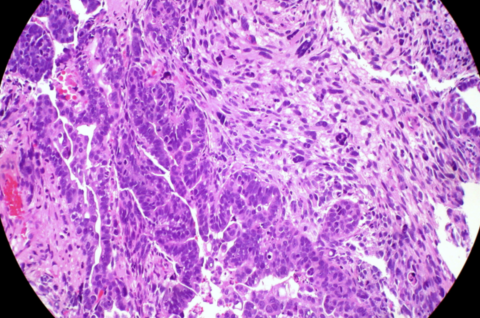

Inhibir la proteïna receptora (CXCR6) d'una molècula anomenada CXCL16 mitjançant fàrmacs o amb edició genètica podria frenar la metàstasi en pacients ...